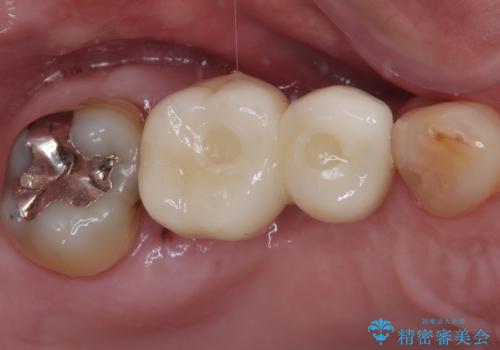

欠損の多い奥歯 インプラントによる補綴治療

- 地元ではなかなかインプラント治療を行ってくださる医院がないとのことで、転勤で東京にいる期間に治療を行いたいとのことで来院された患者様です。

上顎は左右ともに骨が少ない状態であり、特殊なドリルを用いた歯槽骨の拡大や自家骨挙上などを行いながらインプラントを埋入していくこととしました。

右下の銀歯も気になるとのことで、インプラント治療と並行してオールセラミックによるブリッジ補綴治療も行うこととしました。